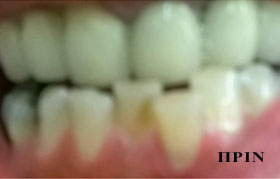

PHOTO GALLERY